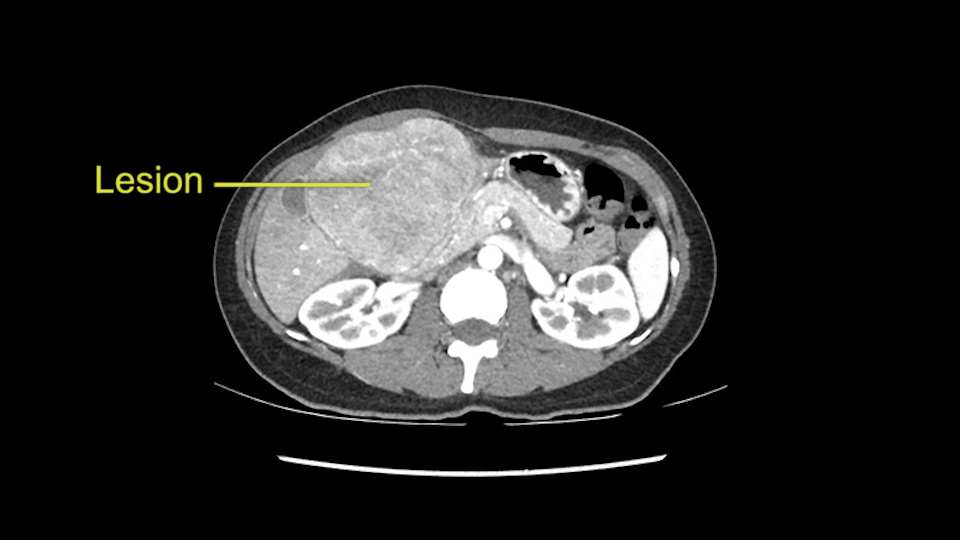

This is a 41 year old woman with chronic Hepatitis B who felt a protrusion in her right upper quadrant. On imaging, a hypervascular liver lesion measuring 9.6 x 9.1 x 9.5cm spanning Segment 4b and 3 was found. Her Alpha-Fetoprotein measured 26000. It is a suspected fibrolamellar HCC/hepatoma or possible benign adenoma. The plan is to perform a left lateral sectionectomy.